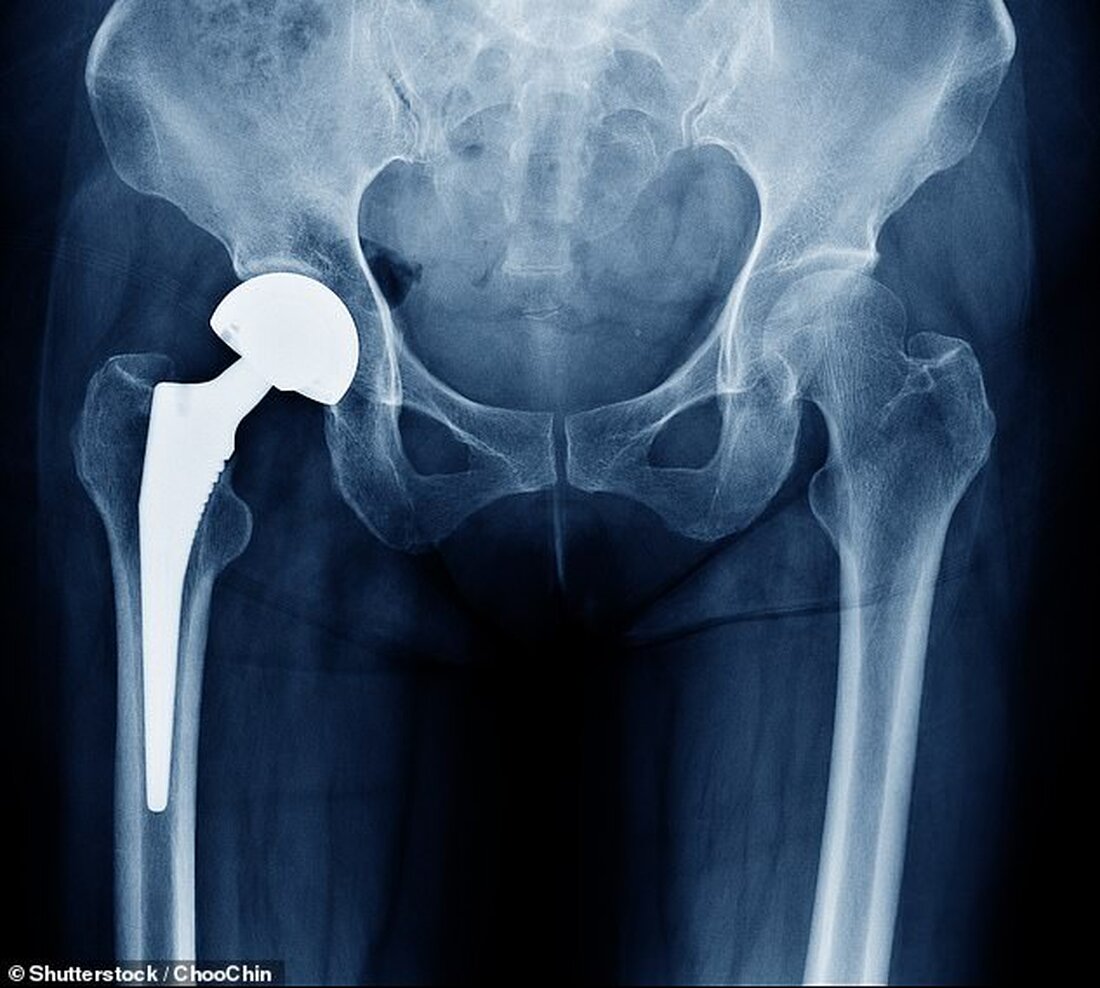

Ein Speichelabstrich vor Ihrem Hüftgelenkersatz könnte vorhersagen, ob das Verfahren funktioniert.

Etwa zehn Prozent der Briten werden sich im Laufe ihres Lebens einer Gelenkersatzoperation unterziehen. Das Verfahren wird häufig verwendet, um Schäden im Zusammenhang mit Arthritis oder altersbedingtem Verschleiß zu beheben.

Gelingt der Gelenkersatz, hält er zwischen 15 und 25 Jahren.